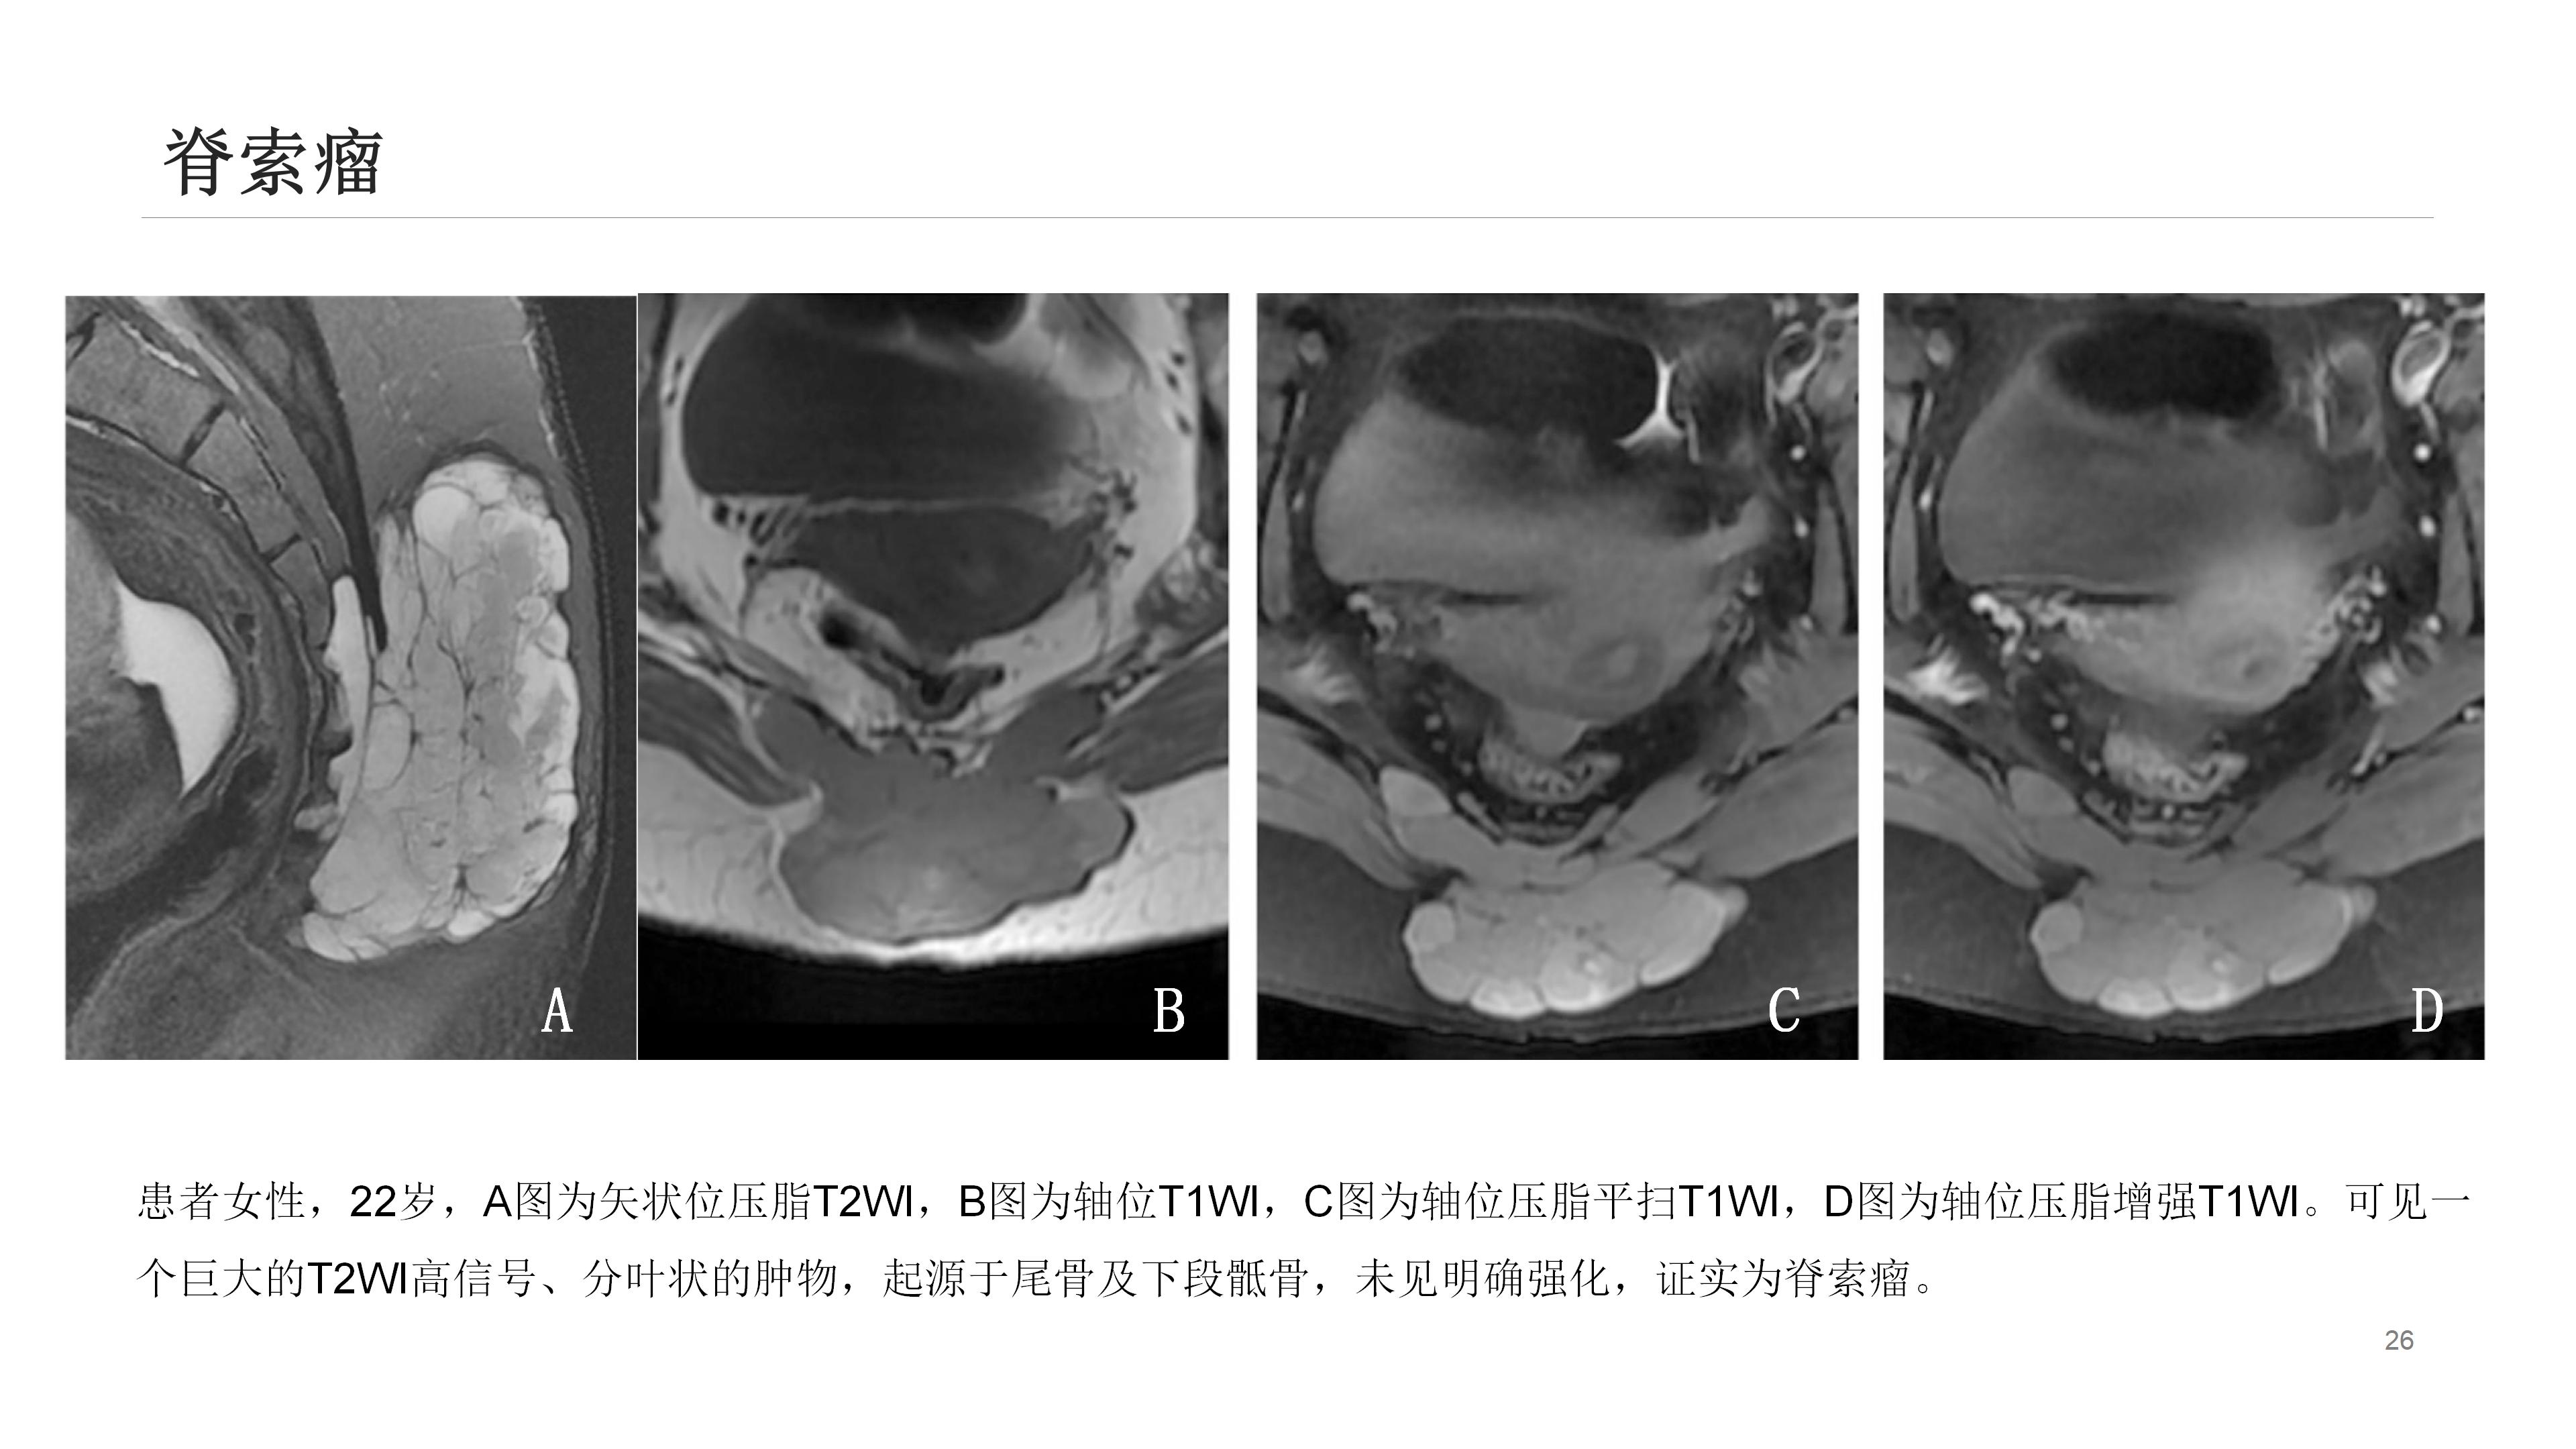

此外,诸如肿瘤、感染、晶体沉积病、囊肿形成(如藏毛囊肿)等其他疾病也可导致尾骨疼痛。